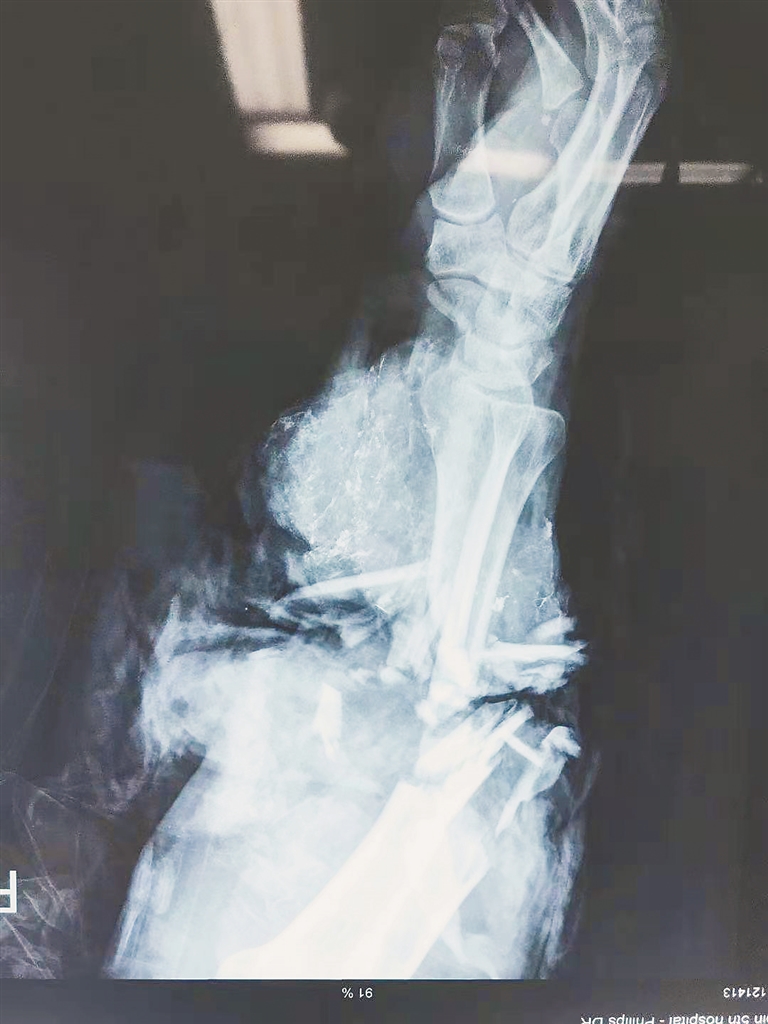

近日,大庆市一男子在操作机器时,机器意外滑落导致右前臂被压断,哈尔滨市第五医院手外科分院医生经过5小时的手术为男子保住断肢。术后,经过一段时间的观察,李先生再植肢体成活完好、血运良好。

“接诊后,我对患者进行了详细的查体,并对伤情进行了评估。当时患者右臂的纱布已经被鲜血浸透,由于患者的创面污染较重,还有金属粉等污染物残留,部分肌肉毁损,并且这种离断伤再植的成活率很低。”手外科分院医生张浩介绍。

张浩医生首先为他进行了右前臂内固定,但这仅仅是整台手术的第一步,最艰难也是最考验医生技术的就是血管的缝合,这也是决定这只手臂能否接活的重要环节。

张浩医生等人将损毁的肌肉清除,对创伤面进行清创处理,找到血管、神经、肌腱的断端,首先缝合断裂的肌肉,这种损伤会有部分静脉撕脱、挫伤较重,这给静脉吻合带来了一定的难度。在显微镜下,医生小心翼翼地将患者的静脉按照顺序依次吻合。松开止血带,各吻合血管血流皆能顺利通过,断臂指端色泽恢复红润,指腹充盈,桡动脉搏动可及。经过5个多小时的努力,医生们将患者离断的手臂血管、神经和肌肉全部成功吻合。术后,患者经过一段时间的观察,再植肢体成活完好、血运良好。